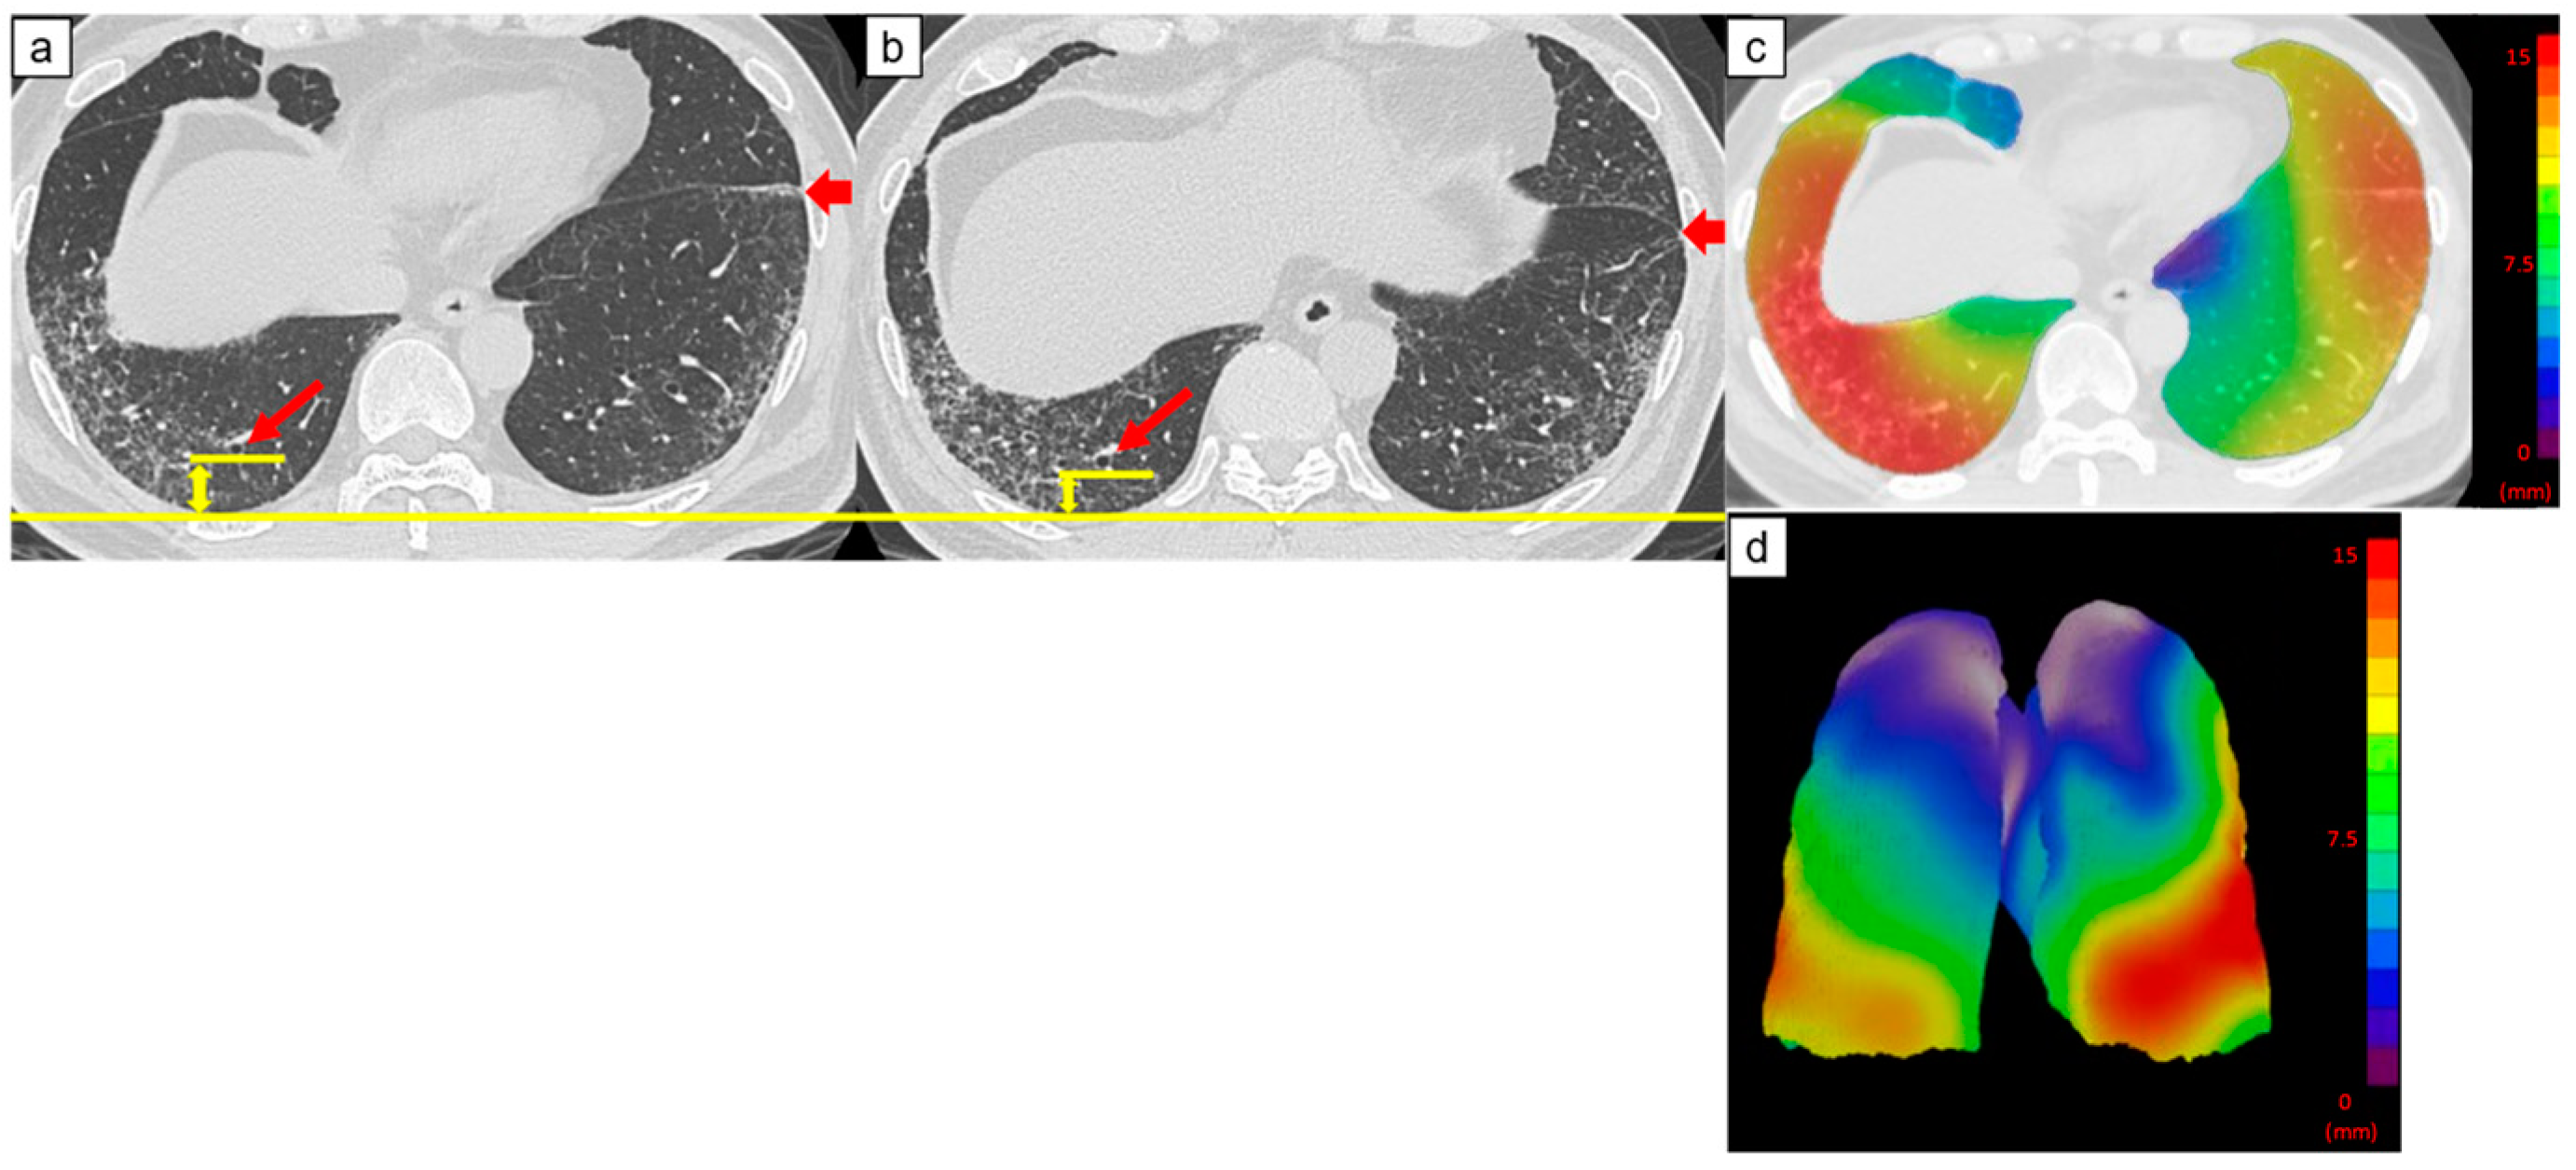

Figure 3.

Computed tomography (CT) images of a 69-year-old man with idiopathic pulmonary fibrosis and three-dimensional average displacement (3D-AD) color maps. (a) Initial CT image of the lung base showed mild subpleural reticulation. (b) Follow-up CT image of the lung base after one year shows increased subpleural reticulation. The fissure deviated backward, indicating the decreased lower lobe volume (thick arrows). The distance between the peripheral bronchi (arrows) and pleura also decreased (yellow lines). (c,d) Color map of the 3D-AD demonstrates greater deviation (red in the color map), corresponding to the subpleural reticulation in the original CT images. In this case, 3D-AD in the subpleural/inner region = 7.4 mm/7.2 mm.